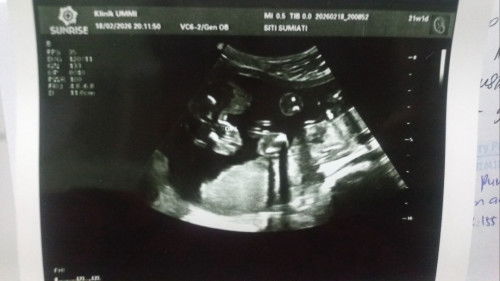

USG 21minggu JK baby girl

Bunda" maaf mau tanya kira" ada yg sama kaya hasil USG aku ga ?! Dibagian JK baby girl seperti itu. Apa itu bentuk vagina ya ? Maaf soalnya baru ini hasil USG JK baby girl alhamdulilah sesuai harapan mudah"an tidak meleset 😇 mohon sharing ya bunda" 🙏 yg hasil USG baby girl. Terima kasih 🙏 #